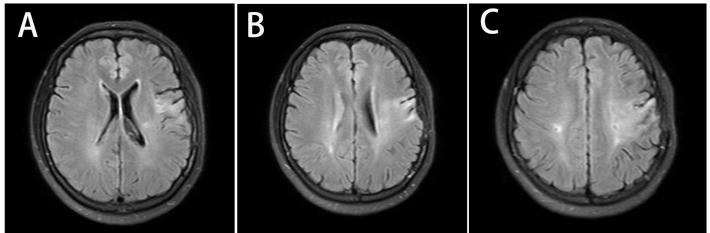

核磁显示双侧多发散在梗塞,左侧严重,与临床症状符合